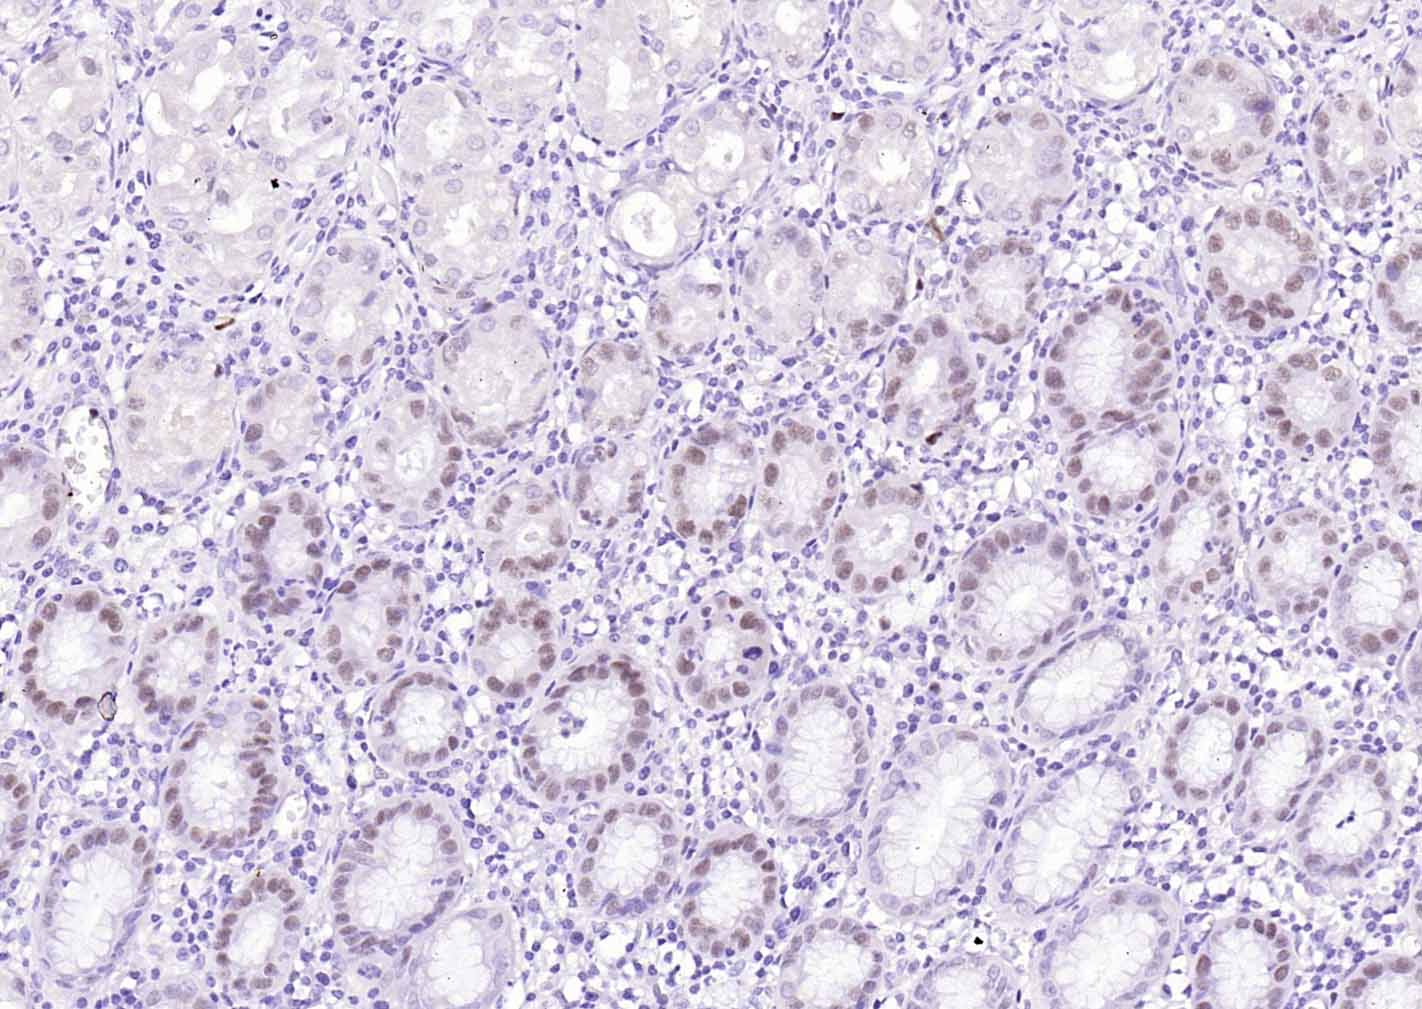

Paraformaldehyde-fixed, paraffin embedded (human stomach); Antigen retrieval by boiling in sodium citrate buffer (pH6.0) for 15min; Block endogenous peroxidase by 3% hydrogen peroxide for 20 minutes; Blocking buffer (normal goat serum) at 37°C for 30min; Incubation with (MCM7 ) Monoclonal Antibody, Unconjugated (bsm-60801R) at 1:100 overnight at 4°C, followed by operating according to SP Kit(Rabbit) (sp-0023) instructionsand DAB staining.